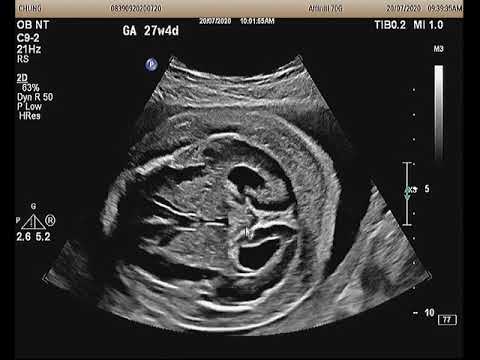

Những điều mẹ bầu cần lưu ý khi thai bị giãn não thất bên

Trẻ em bị giãn não thất thường với triệu chứng: vòng đầu tăng nhanh, đau đầu, chán ăn, hay ói mửa, thay đổi hành vi và tính cách, thay đổi thói quen, suy giảm trí tưởng, mất tập trung, mỏi mệt, thất đ